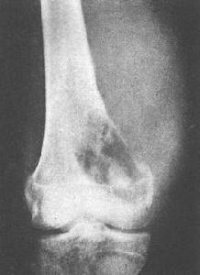

X线表现为骨性病损自干骺端突出,一般比临床所见的要小,因软骨帽和滑囊不显影,肿瘤的骨质影像与其所在部位干骺端的骨质结构完全相同。不易区别。位于长骨的肿瘤其生长方向与邻近肌肉牵引的方向一致,例如股骨远端的骨软骨瘤向股骨的生长,胫骨近端的肿瘤向胫骨远端生长。其形状不一,可有一个很长的蒂和狭窄的基底。或很短粗呈广阔的基底,较大的肿瘤其顶端膨大如菜花,悬垂状骨性骨块,其尖端朝向邻近关节相反方向。其基底直接或有一细蒂与骨皮质相连续。瘤体表面的软骨帽虽然在X线上不显影,但常有钙化和骨化位于前臂小腿的较大肿瘤可压迫邻近骨骼,产生压迫性骨缺损或畸形。多发性者往往合并骨骼畸形。

1.X线表现:表现为附着于干骺端的向外骨性突起,生长方向与肌肉的牵引方向一致,与受累骨皮质和松质骨相连,软骨帽不显影,有长蒂型和广基型之分。

多发性骨软骨瘤表现为干骺端增粗,皮质变薄,肿瘤外形不一,常出现患骨关节畸形,当肿瘤恶变时,其表面的软骨部分迅速长大,当有大量钙化时,则X线表现明显。